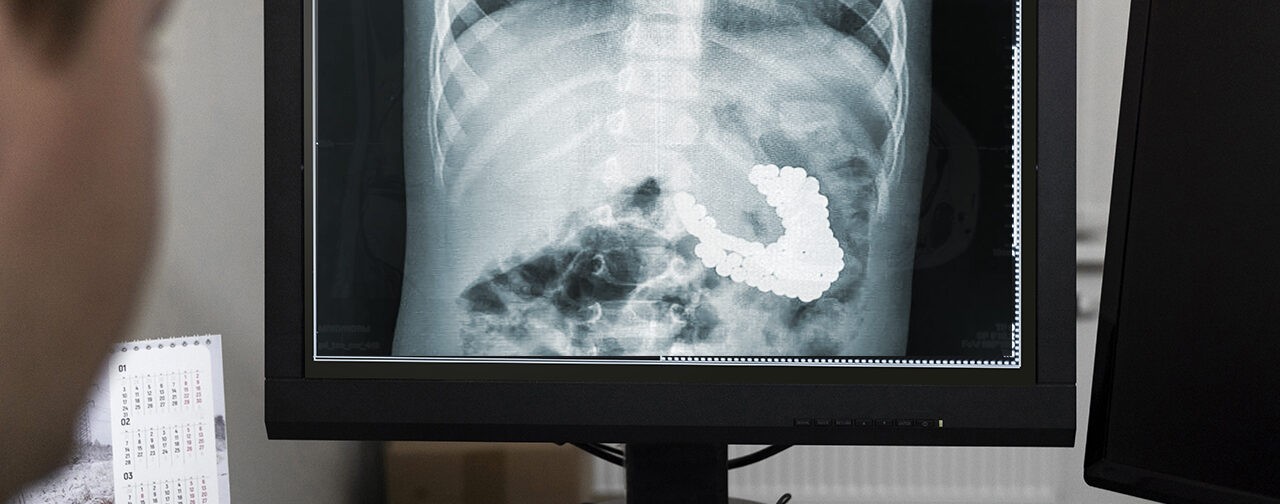

«После операции выполнили контрольную рентгенографию и обнаружили еще три магнита, которые невозможно было удалить с помощью эндоскопа. Ребенок глотал магниты в разное время, поэтому некоторые из них уже переместились в кишечник. Находясь там, они сцепились и притянули друг к другу желудок и кишечник. Извлечь оставшуюся часть можно было только хирургическим путем», — рассказал заведующий эндоскопическим отделением Александр Иноземцев.

В апреле 2024 года в Ленинградской области двухлетний мальчик проглотил 124 магнита, операцию ему провели в детской клинической больнице. «Магниты слиплись в ком размером с нектарин», — рассказала врач изданию 47news. Операция длилась около двух часов.